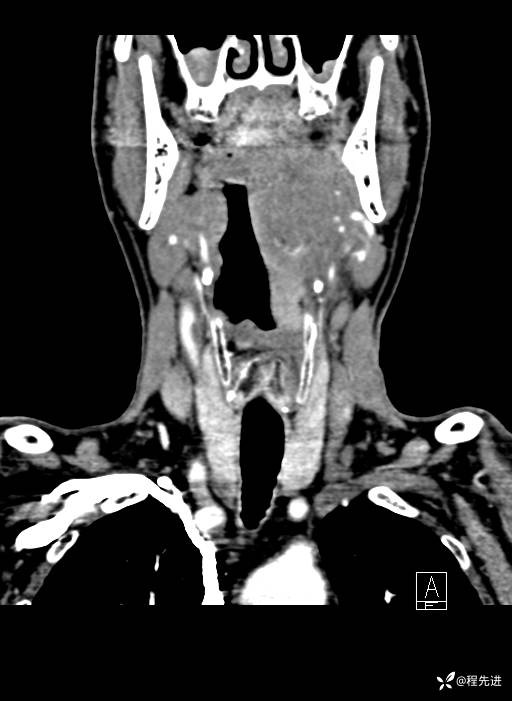

CT平扫:

CT增强:

静脉期:

增强冠矢状位重建: